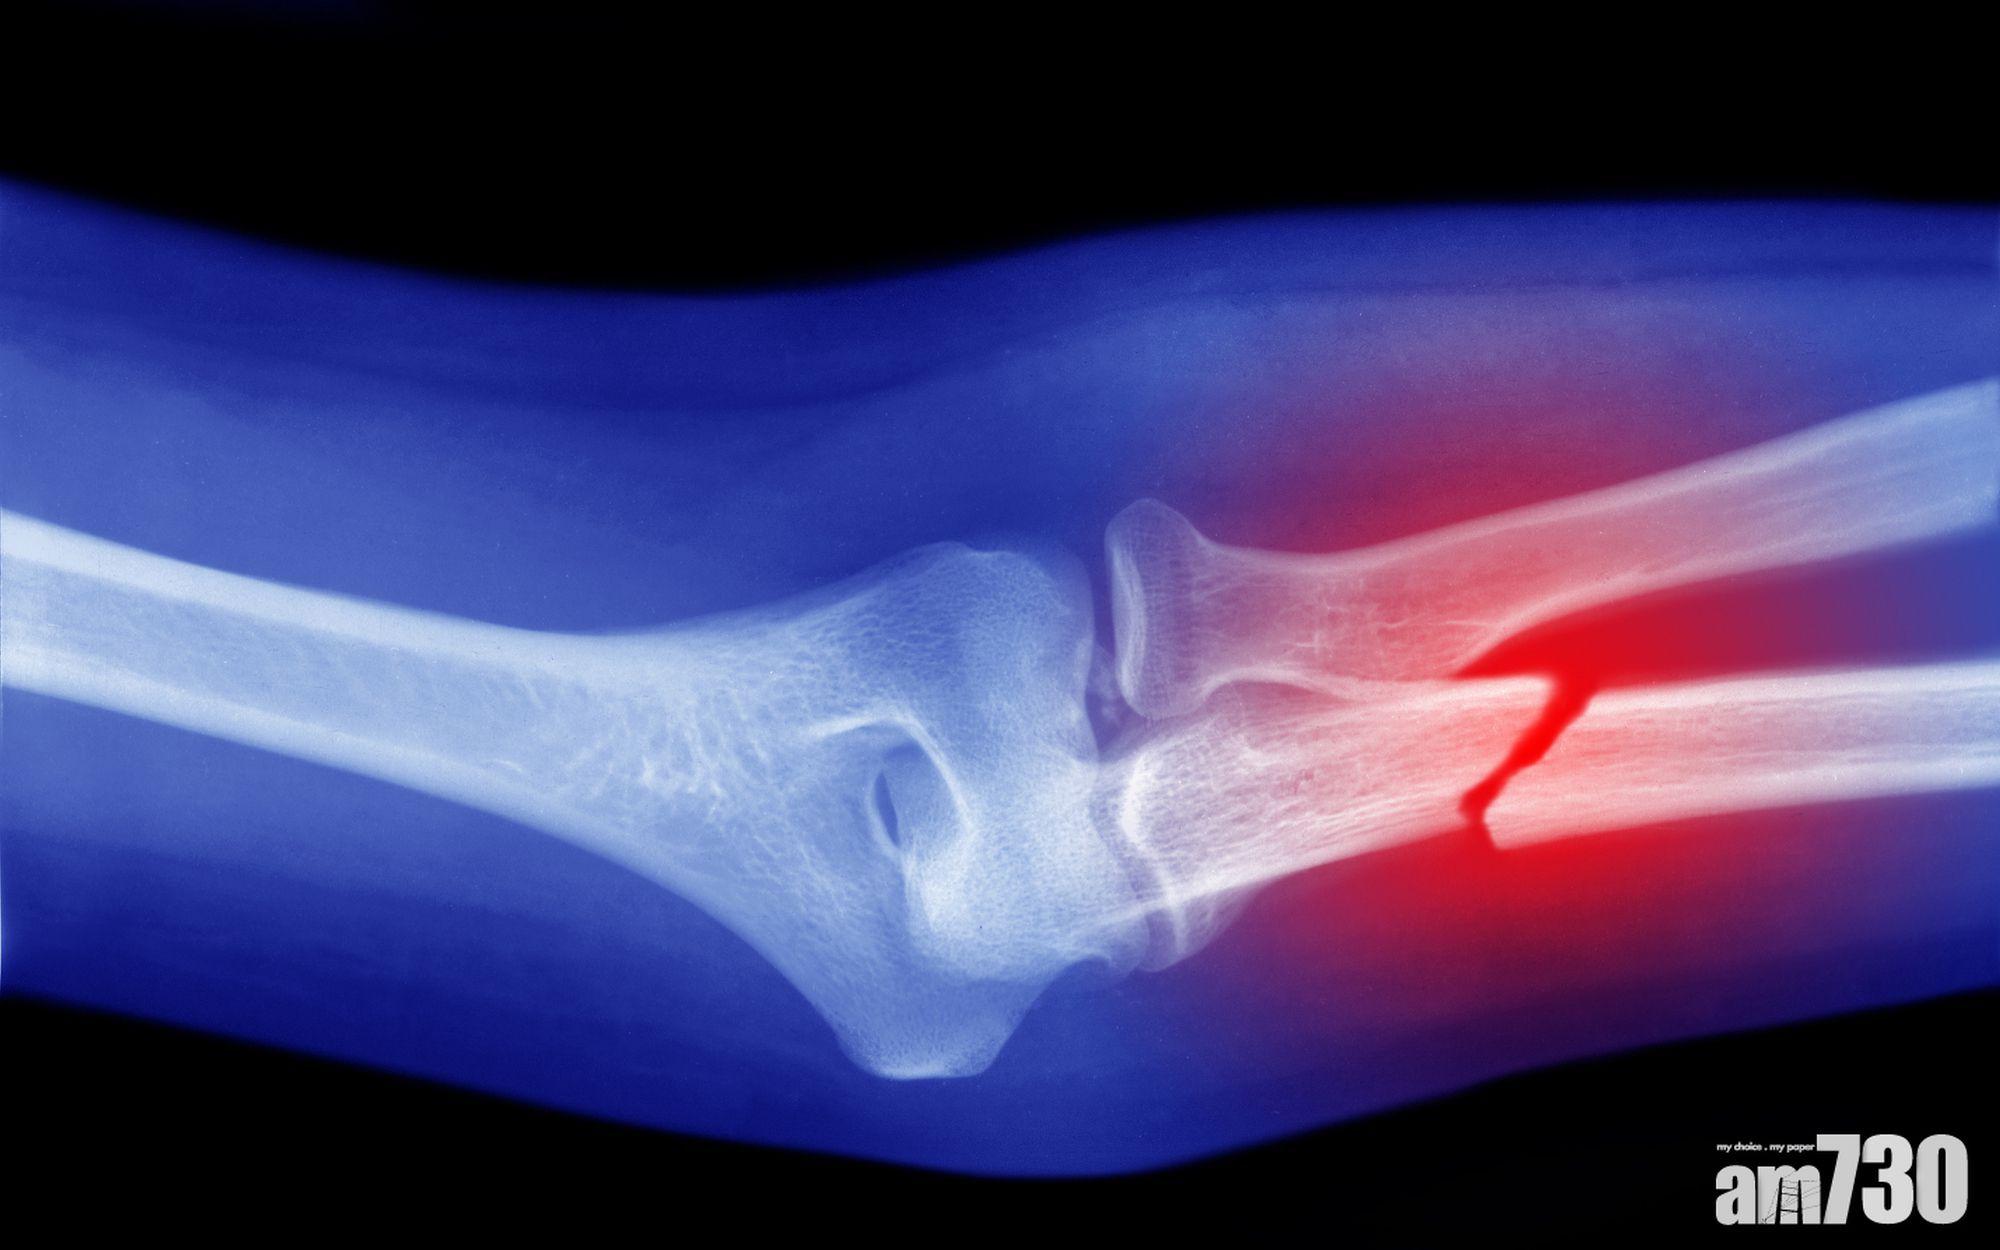

骨折|港大發現鎂離子免疫調控機制 促進骨骼愈合

雖然骨骼組織在受傷之後可以自我修復及再生,但是愈合過程需時,亦難以完全恢復受傷前的結構和力學特性。鎂離子在骨折愈合過程中有其角色,但部分研究指可刺激骨骼組織再生;亦有報道表示鎂合金植入體在降解時,鎂離子卻造成骨骼組織嚴重損傷。港大醫學院研究團隊便為此作出鎂離子角色的剖析。

不同的鎂離子遞送策略對大鼠股骨缺損創傷修復的影響。